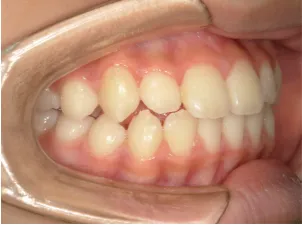

治療中➁小3:9y8m QH、BH、前歯並び替え終了

治療中③小4:10y8m モノブロック・MFT継続中

治療中④小5:11y9m モノブロック装置継続中 MFT継続中

治療中⑤小6:12y8m モノブロック装置継続中 MFT継続中

治療中⑥中1:13y3m 左側奥歯の咬み合わせ改善のため一時クロスゴム併用